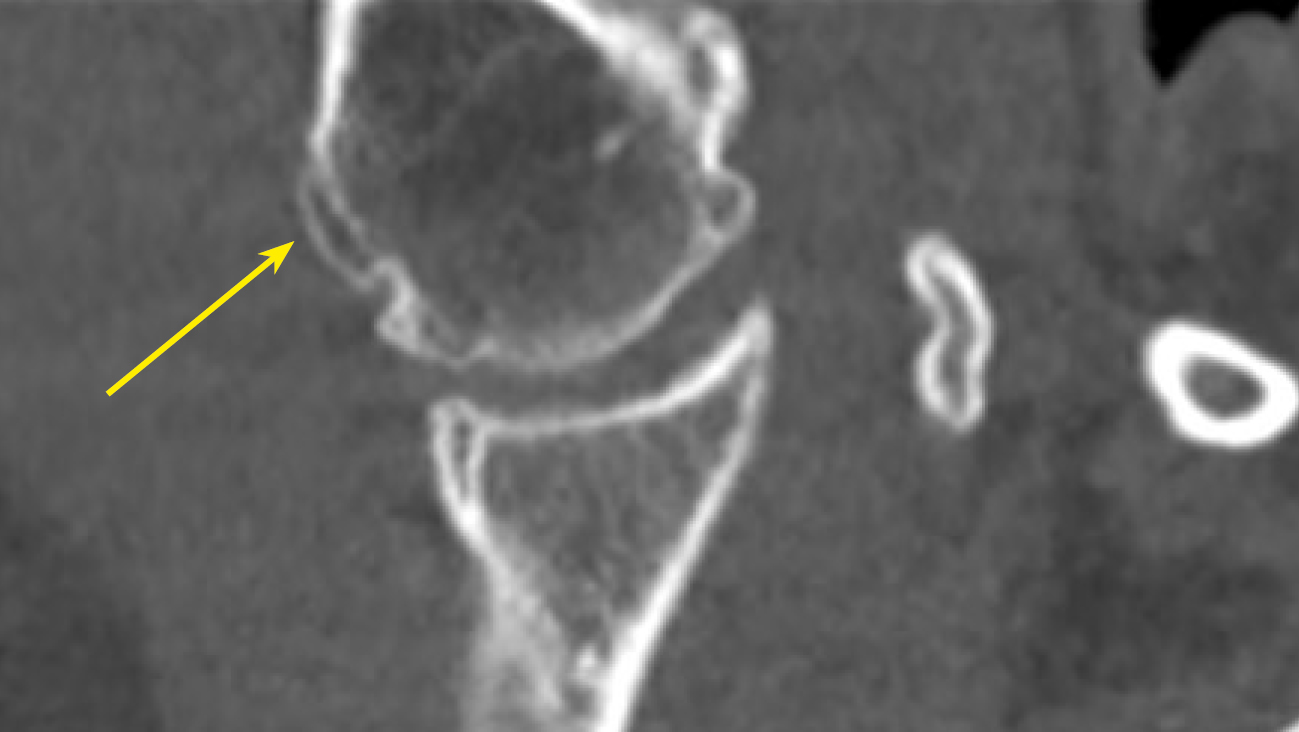

В нашем исследовании проведен анализ патологии позвоночника и суставов у пациентов с акромегалией. Спондилоартроз выявлен почти у всех пациентов — 95,9%, чуть реже визуализирован ОА реберно-позвоночных суставов 89,8% и ОА грудино-реберных суставов в 75,9% случаев (табл. 3, рис. 2–5).

Рисунок 3. МСКТ пациента А. с акромегалией 37 лет, коронарная проекция. ОА плечевого сустава, грубые костные разрастания по контурам головки плечевой кости (стрелка).

Figure 3. MSCT of patient A. with acromegaly, 37 years old, coronal view. OA of the shoulder joint, rough bone growths along the contours of the humeral head (arrow).